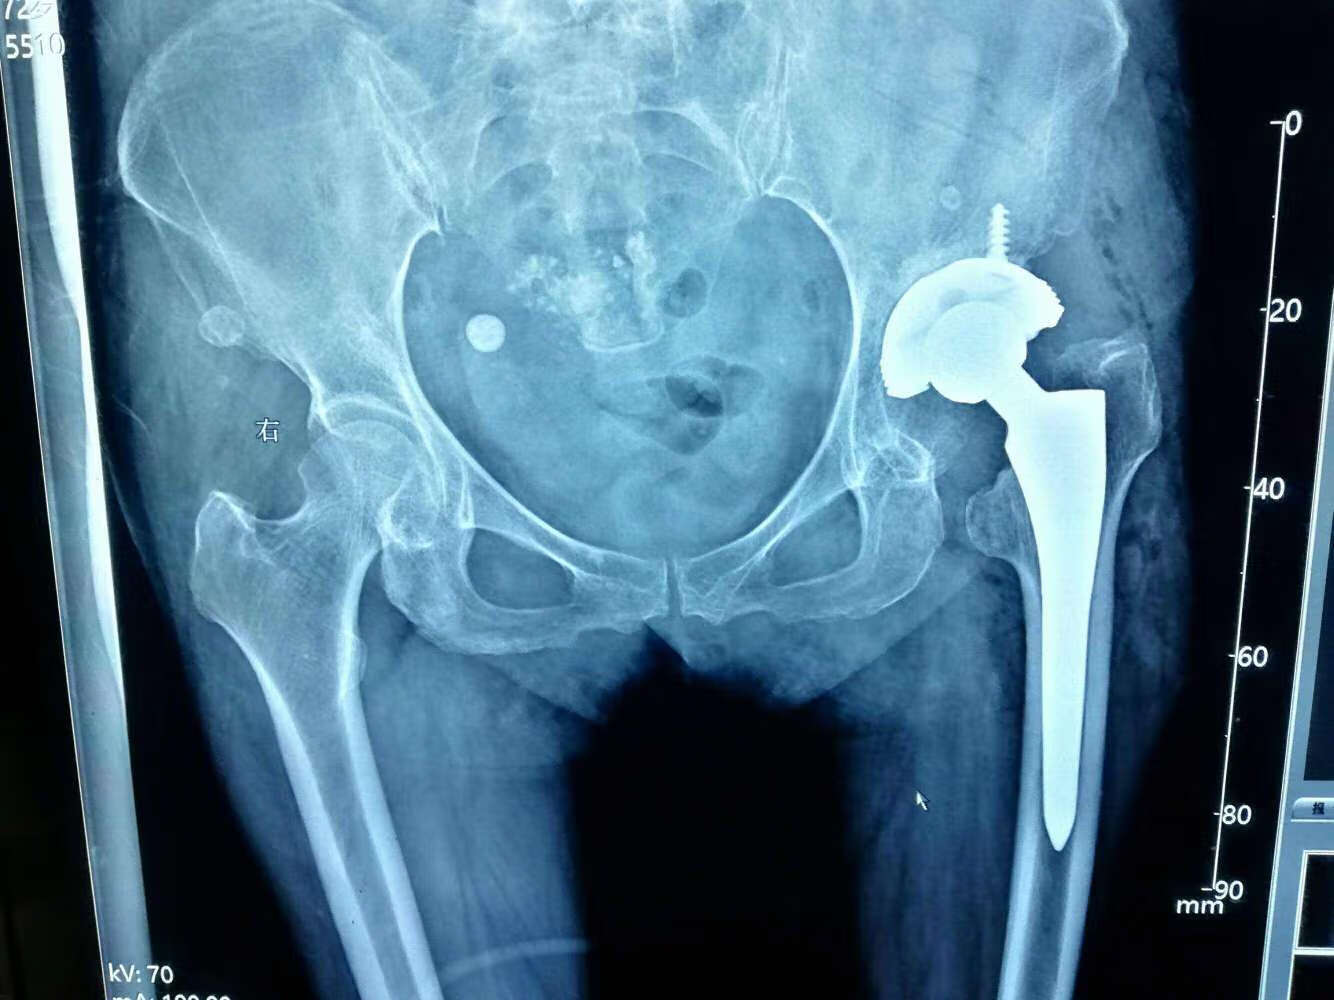

股骨头坏死的早期症状包括髋关节疼痛、活动受限和关节僵硬等,通常在患者感到明显不适后,才会寻求医疗帮助。针对股骨头坏死,股骨头坏死保守治疗逐渐受到关注。衡水股骨头医院具备先进的治疗理念和专业的医师团队,能够为患者提供个性化的保守治疗方案。这种疗法有助于缓解由股骨头疼痛的症状引发的不适,且在早期阶段具有一定的康复潜力。

衡水股骨头医院在治疗股骨头疼痛方面具备多项优势。首先,医院拥有专业的医疗团队,致力于研究和实践股骨头坏死保守治疗的方法。通过个性化的诊疗方案,该院能够为患者提供针对性强的医疗服务。其次,医院配备了先进的医疗设备和技术,以确保准确的诊断和治疗。此外,患者普遍反映在这里接受治疗后,症状明显减轻,并在康复过程中得到了良好的支持与指导。通过分享成功案例,患者能更直观地感受到医院在康复方面的卓越表现。这些因素共同促使越来越多的江西省股骨头坏死患者选择衡水股骨头医院进行治疗,为他们提供了信心与希望。

在衡水股骨头医院,许多患者通过保守治疗取得了康复效果。医院内的病友分享了他们的经历,强调了早期发现和专业指导对股骨头坏死症状缓解的重要性。许多患者反映,接受治疗后疼痛感减轻,有些患者在持续锻炼下成功恢复了日常生活能力。这表明,即使是初期的股骨头坏死,通过科学的康复方法和适当的锻炼,仍有可能达到较理想的疗效。医院配备的专业团队与积极的患者反馈,使得越来越多的人选择到这里寻求帮助,从而形成稳定而良好的口碑。这种积极转变也吸引了更多新患者前来咨询与就医。